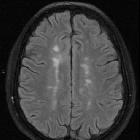

Dawson fingers are a radiographic feature of demyelination characterized by periventricular demyelinating plaques distributed along the axis of medullary veins, perpendicular to the body of the lateral ventricles and/or callosal junction. This is thought to reflect perivenular inflammation. They are a relatively specific sign for multiple sclerosis.

Radiographic features

MRI

- T1: low signal in chronic lesions; otherwise usually isointense to white matter

- T2/FLAIR: linear or ovoid high signal

- T1C+ (Gd): enhancement can be seen with active lesions